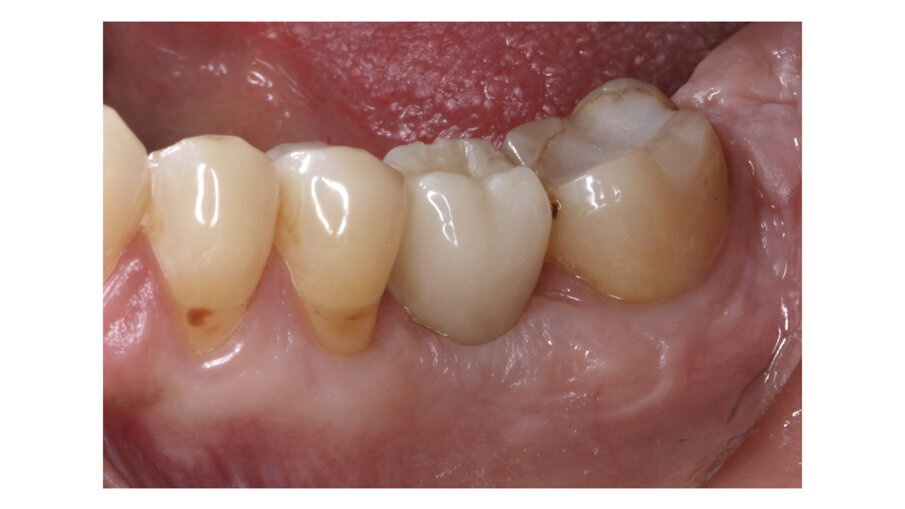

Fig. 4: Implant crown after one week of placement.

Fig. 5: Implant crown after placement.